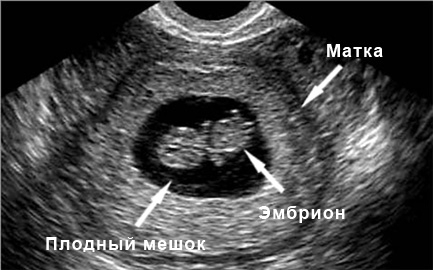

На этом этапе ультразвуковое исследование уже может зафиксировать наличие беременности. Она выглядит как маленький черный кружок, диаметр которого составляет всего несколько миллиметров. Это плодный мешок. На четвертой неделе беременности ультразвуковая диагностика также показывает расширение сосудов матки, что является нормальным явлением.

УЗИ: 5-ая неделя беременности

Теперь будущий малыш выглядит как овал с хвостиком и головой. На этом этапе ультразвуковое исследование уже четко фиксирует его. Врачи начинают называть его эмбрионом. Сердце, а также спинной и головной мозг активно развиваются. УЗИ показывает явные сокращения формирующегося сердца. Однако это еще не то сердце, к которому мы привыкли; на данный момент оно представлено в виде двух сокращающихся каналов, известных как сердечные трубки.